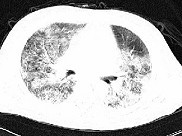

单项选择题男性,42岁, 近2年来无明显诱因反复出现咳嗽,痰少, 活动后气促,无发热, 无胸痛,无咯血, 心电图及心脏彩超未见异常,肺功能FEV1.901, FVC2.001,DLco下降, 支气管激发试验阴性。胸部CT见图,该患者最有可能是下列哪一种疾病 ( )

E、特发性间质性肺炎